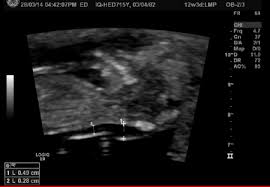

What Does A Normal Nt Scan Mean / Nuchal Scan Paras / A nuchal scan or nuchal translucency (nt) scan / procedure is a sonographic prenatal screening scan (ultrasound) to detect chromosomal abnormalities in a fetus, though altered extracellular matrix composition and limited lymphatic drainage can also be detected.. Nuchal translucency scan the nuchal scan (nt scan) is a screening done during an antenatal ultrasound to measure the amount of fluid at the base of your baby's neck. Another test offered by some hospitals is a nuchal translucency scan performed during a dating scan. A nuchal translucency scan is part of the ultrasound scan that most pregnant women have at around 12 weeks of pregnancy. This test measures the size of the clear tissue, called the nuchal translucency, at the back of your. It can be a very scary time but it doesn't mean anything is wrong and the fact that it was 3.6 is good bc that's not that much more than normal.

The 11 14 Week Scan Chapter 1 from sonoworld.com It should not be confused with the nuchal fold, which is seen in the second trimester. But many babies with down's syndrome have an increased amount. That's why the nt scan is used to help screen for down's syndrome. I'm still waiting for my follow up appointment after my scan results which my gp has said look normal. As i'm 3 months late for this appointment i rang the hospital and spent over an hour getting absolutely nowhere. The first trimester screen won't harm you or your baby. The nt scan measures the thickness of the fluid at the back of your baby's neck. It is a special ultrasound scan which is performed to specifically measure a tiny bit of fluid that lies under the baby's skin behind the neck known as the nuchal translucency (nt).

It helps doctors determine if a baby is statistically more likely to have a chromosomal abnormality. Nuchal translucency scan the nuchal scan (nt scan) is a screening done during an antenatal ultrasound to measure the amount of fluid at the base of your baby's neck. Nuchal translucency (nt) is a collection of fluid under the skin at the back of your baby's neck. Between 11 weeks and 13 weeks plus six days of pregnancy or when your baby measures between 45mm and 84mm, crown to rump All developing babies have some fluid at the back of their neck. The result is screen positive if the likelihood of down syndrome in the first trimester is one in 230 or greater. It doesn't always mean a chromosomal problem. The nt scan measures the thickness of the fluid at the back of your baby's neck. And when the crl is 84mm, the normal nt range is from 1.9 to 2.7mm. Some hospitals offer first trimester bloods instead of the 15 to 16 weeks blood tests. Nuchal translucency (nt) is a collection of fluid under the skin at the back of a baby's neck. An nt scan is a common screening test that occurs during the first trimester of pregnancy. An increased nt measurement does not always mean the baby has a problem but it does increase the risk.

An nt measurement of less than 3.5mm is considered normal. The result is screen positive if the likelihood of down syndrome in the first trimester is one in 230 or greater. As i'm 3 months late for this appointment i rang the hospital and spent over an hour getting absolutely nowhere. Doctor said if there was no chromosomal abnormality there could be a potential heart defect. To be more precise, the normal nt ranges from 1.2 to 2.1mm when the crl is 45mm.

The 11 14 Week Scan Chapter 2 from sonoworld.com Some babies with increased fluid don't have down syndrome or any other abnormality. This is when they measure the fluid at the back of the baby's neck. The nuchal translucency normal range chart is a guideline during this scan. But if it is between 3 and 3.5mm, then it is considered high (6) (7). An nt scan is a common screening test that occurs during the first trimester of pregnancy. To be more precise, the normal nt ranges from 1.2 to 2.1mm when the crl is 45mm. Also, a negative or normal result (one that shows a decreased risk) does not mean that the baby will not have a chromosome abnormality. There are a lot of things that can cause a large nt, including a chromosomal abnormality or heart defect or nothing at all.

A nuchal translucency scan is part of the ultrasound scan that most pregnant women have at around 12 weeks of pregnancy. When the nt is greater than 3.5 mm, there is a 1 in 5 chance of a chromosome abnormality such as turner or down syndrome, or trisomy 18.additional tests should be ordered by an ob or genetic counselor for confirmation. Heart was strong at 156, and baby was showing me its 10 fingers and 10 toes ️ the elation of seeing my baby quickly flew out the window when the doctor told me the nuchal fold was measuring at 4.5mm which is above the 3mm it should be right now. I'm still waiting for my follow up appointment after my scan results which my gp has said look normal. About one in every 20 women screened will be in this group. I had a normal nt scan of 1.33mm, but had a 1:153 risk ratio for trisomy 21.but my hospital did not give me an overall combined risk ratio with the nt for down syndrome. Some babies with increased fluid don't have down syndrome or any other abnormality. I am 12wks5dys and had my nt scan today. It can be a very scary time but it doesn't mean anything is wrong and the fact that it was 3.6 is good bc that's not that much more than normal. An nt scan is a common screening test that occurs during the first trimester of pregnancy. Also, a negative or normal result (one that shows a decreased risk) does not mean that the baby will not have a chromosome abnormality. It helps doctors determine if a baby is statistically more likely to have a chromosomal abnormality. The nt measure is then analyzed per the gestational age and maternal age to know the risks of abnormality.

The nt scan measures the thickness of the fluid at the back of your baby's neck. I had a normal nt scan of 1.33mm, but had a 1:153 risk ratio for trisomy 21.but my hospital did not give me an overall combined risk ratio with the nt for down syndrome. It is a special ultrasound scan which is performed to specifically measure a tiny bit of fluid that lies under the baby's skin behind the neck known as the nuchal translucency (nt). Between 11 weeks and 13 weeks plus six days of pregnancy or when your baby measures between 45mm and 84mm, crown to rump The nt scan is an ultrasound done in the first trimester to determine your baby's risk of having down syndrome and some other chromosomal abnormalities.

Nuchal translucency scan the nuchal scan (nt scan) is a screening done during an antenatal ultrasound to measure the amount of fluid at the base of your baby's neck. It helps doctors determine if a baby is statistically more likely to have a chromosomal abnormality. A nuchal translucency scan is part of the ultrasound scan that most pregnant women have at around 12 weeks of pregnancy. Some hospitals offer first trimester bloods instead of the 15 to 16 weeks blood tests. Nuchal translucency (nt) is a collection of fluid under the skin at the back of a baby's neck. A maternal blood sample will also be taken and you may also be offered an evaluation of the baby's nasal bone. Also, a negative or normal result (one that shows a decreased risk) does not mean that the baby will not have a chromosome abnormality. If the screen indicates that your baby may have a problem, you can decide whether or not to have cvs or amnio for a diagnosis. I'm 28 weeks now and baby's heart looks completely normal. A nuchal scan or nuchal translucency (nt) scan / procedure is a sonographic prenatal screening scan (ultrasound) to detect chromosomal abnormalities in a fetus, though altered extracellular matrix composition and limited lymphatic drainage can also be detected. Thickness of the translucency varies with gestational age: It is a special ultrasound scan which is performed to specifically measure a tiny bit of fluid that lies under the baby's skin behind the neck known as the nuchal translucency (nt). This is when they measure the fluid at the back of the baby's neck.